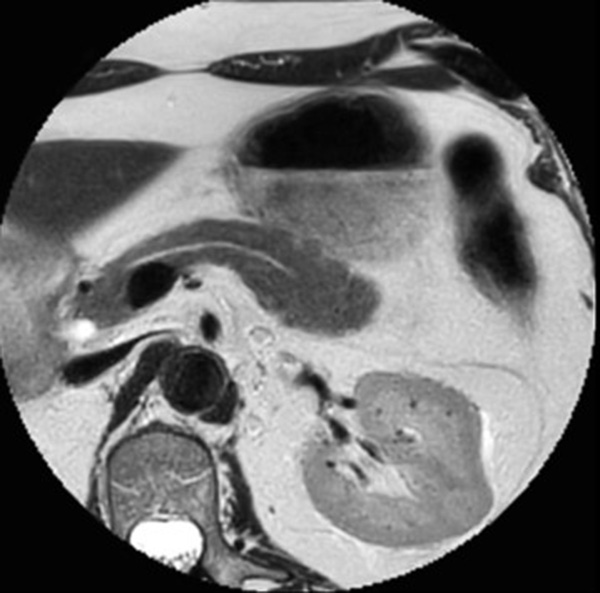

Pancreas imaging with dS Zoom